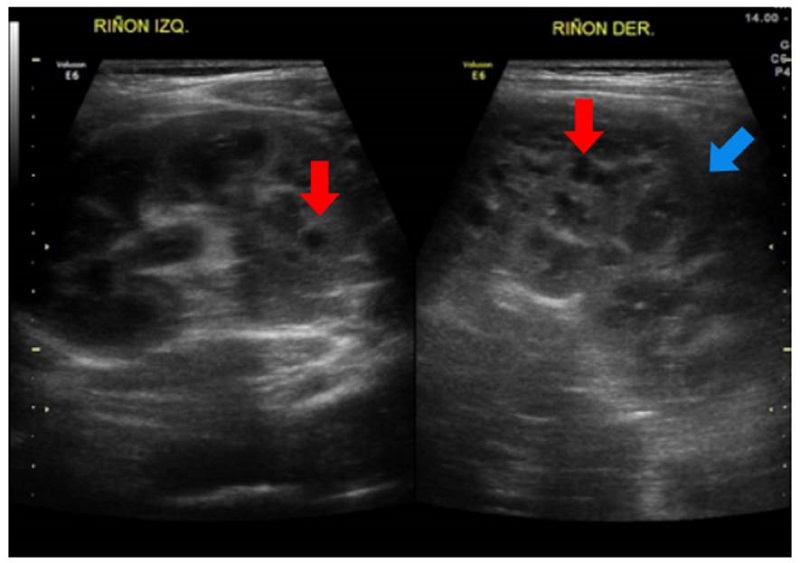

Se trató de una paciente de sexo femenino, producto de una unión no consanguínea, sin antecedentes familiares de enfermedad renal, en quien se documentó nefromegalia bilateral asociada con poliquistosis renal bilateral desde el primer año de vida (figura 4). Se inició terapia de reemplazo renal a los seis años de vida, y fue sometida a nefrectomía bilateral y trasplante renal con donante vivo relacionado, a los ocho años. En el estudio histopatológico se informó adelgazamiento cortical con disminución del número de glomérulos y reemplazo del parénquima por lesiones quísticas. Al aplicar un panel de secuenciación de nueva generación para enfermedad poliquística renal, no se demostraron variantes patogénicas asociadas con el cuadro clínico de la paciente. Actualmente, a los 17 años, la paciente continúa en seguimiento con tratamiento inmunosupresor, función renal estable, sin hipertensión arterial y sin alteraciones del estado ácido-base ni de los hidroelectrolíticos. Una ecografía abdominal reciente no mostró lesiones hepáticas.

Análisis. De los pacientes con enfermedad poliquística renal de herencia autosómica recesiva, entre el 30 y el 40 % fallece por complicaciones asociadas con hipoplasia pulmonar en el periodo neonatal 2. El 75 % de los pacientes presenta hipertensión arterial sistémica, predominante en los primeros meses de vida, y el 60 % desarrolla enfermedad renal terminal a los 20 años 18.